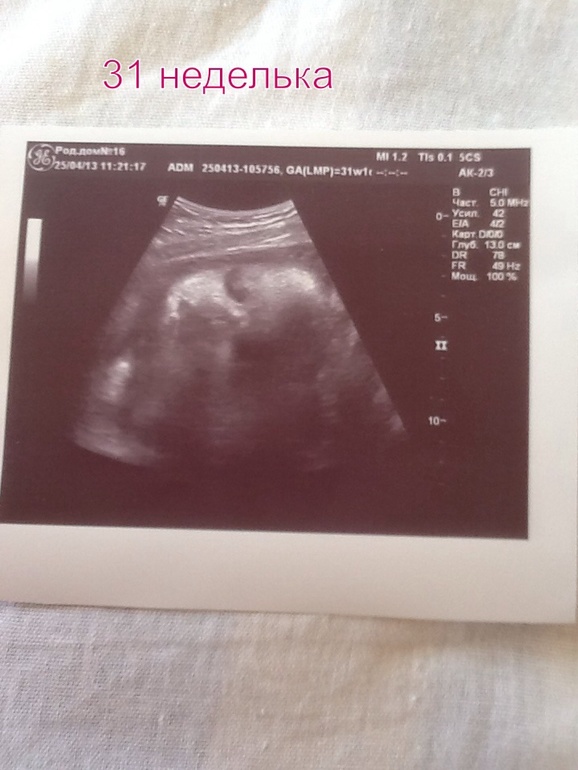

все хорошо))) Слезы радости хотелось кричать и прыгать от радости!!!!! А в 31 неделю на узи наша принцесса показала нам свое личико)))